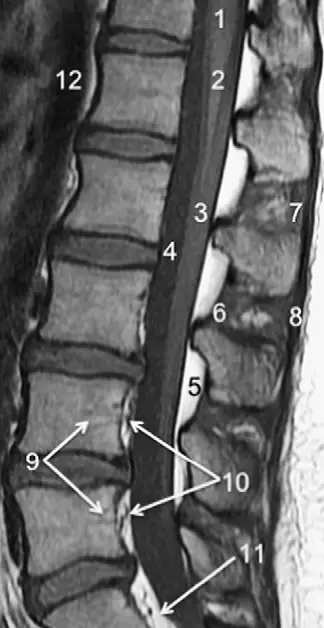

腰椎磁共振解剖图谱

腰椎磁共振解剖图谱,腰椎磁共振解剖

腰椎mri解剖图

胸,腰椎mri解剖图谱,新手必备

影像解剖 | 颈胸腰椎mri解剖图谱,人人必备

腰椎磁共振解剖

腰椎磁共振图解

腰椎磁共振图片

正常腰椎磁共振图片

腰椎解剖图谱

腰椎磁共振

正常腰椎磁共振

新手看腰椎核磁图解

正常腰间盘核磁共振图

正常人的腰椎核磁图片

腰椎图谱

正常腰椎ct图